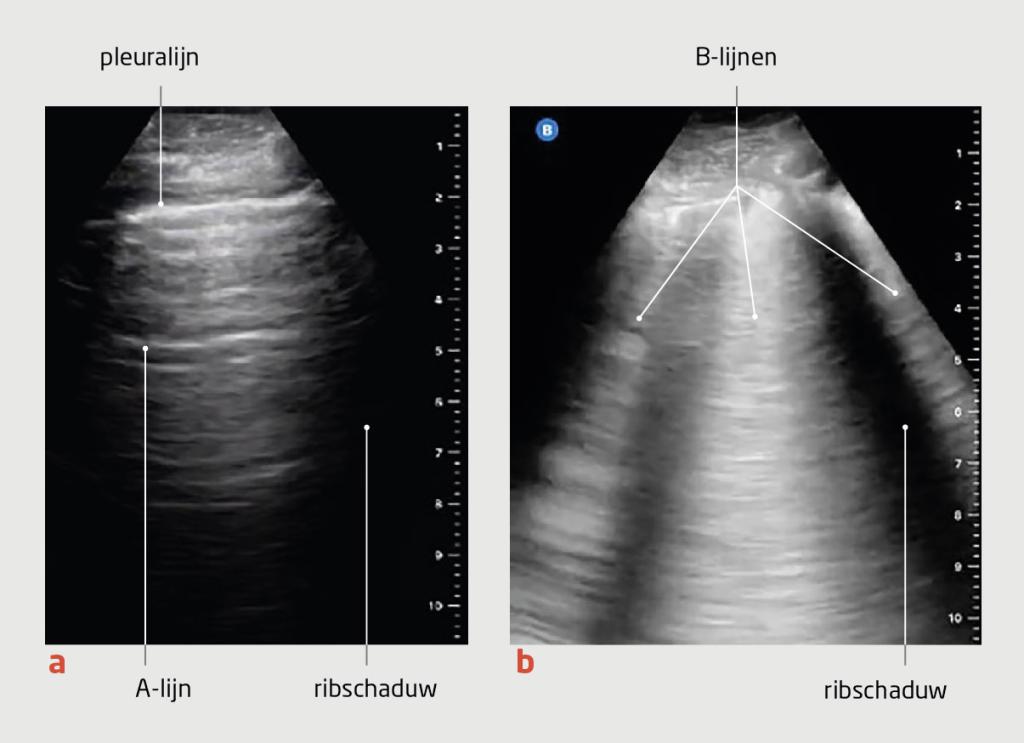

• Het combineren van conventionele methoden met eenvoudig toepasbare point-of-care-echografie (POCUS) helpt om de vullingsstatus nauwkeuriger vast te stellen. Bij dit POCUS-onderzoek beoordeelt men het punt van collaps van de v. jugularis interna, de diameter van de proximale v. cava inferior en de aanwezigheid van pulmonale B-lijnen.